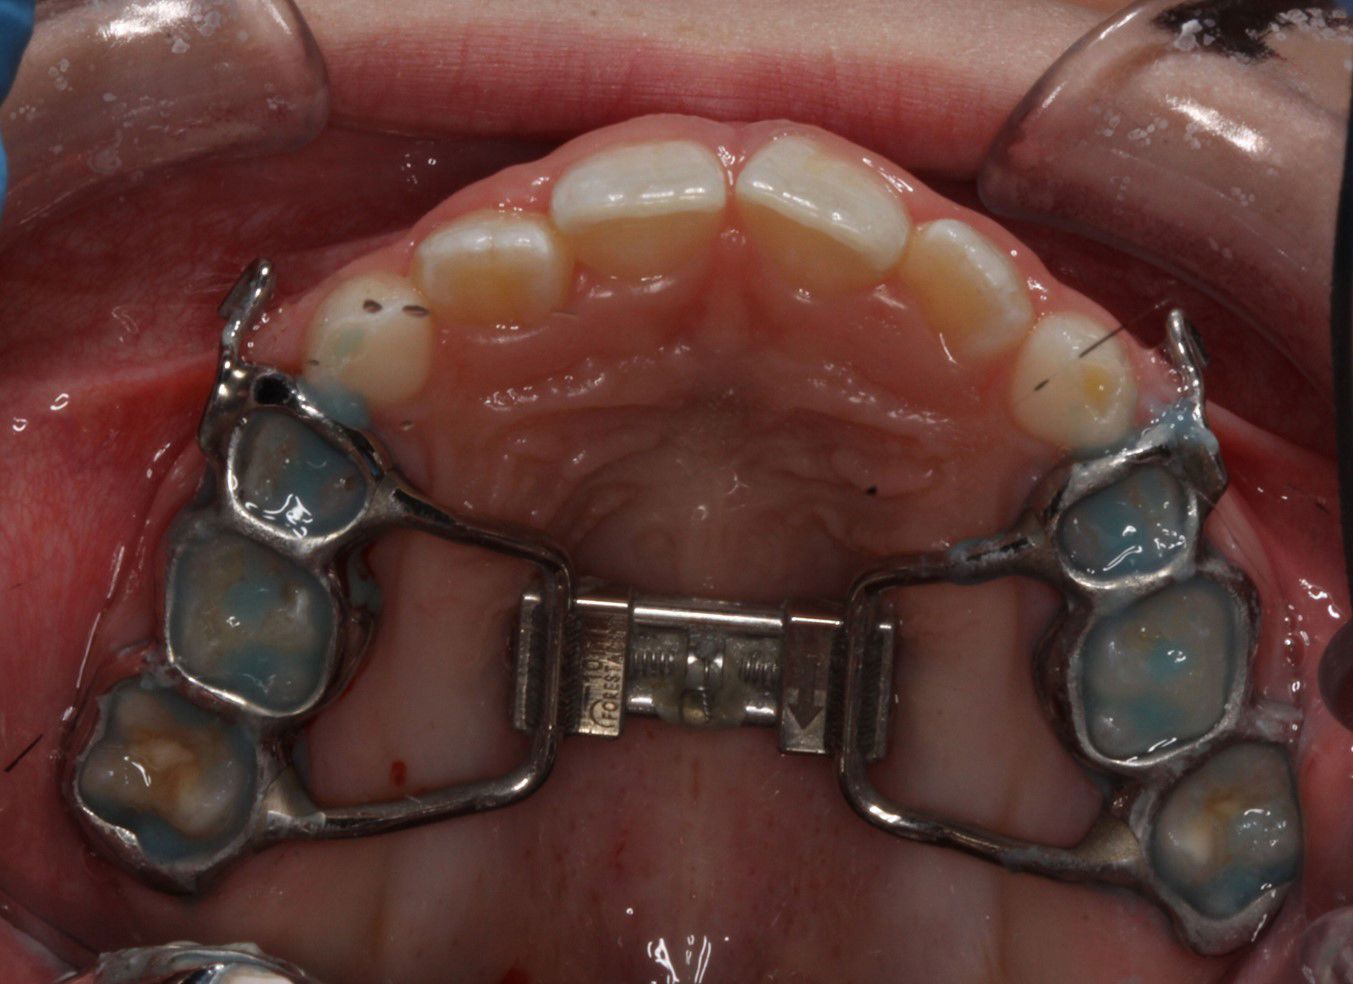

Bruges til at udvide tandbuen i overkæben, f.eks. ved krydsbid.

Den er fastgjort til 6-års tænderne med 2 bånd.

Bruges til at udvide ganen.

Den limes fast på tænderne. Der skal skrues i midten af bøjlen, I får en grundig instruktion på tandreguleringsklinikken.

Der kan opstå lidt spænding ved tænderne, næsen og evt. mellem øjnene.

Ofte kommer der et mellemrum ved fortænderne i en periode.